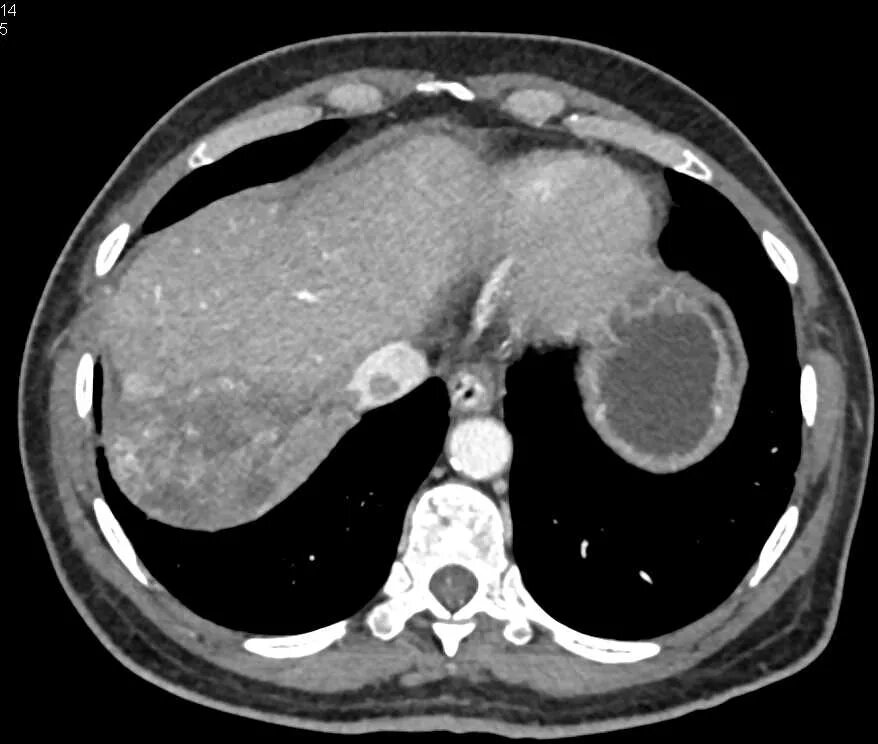

Забрюшинная онкология